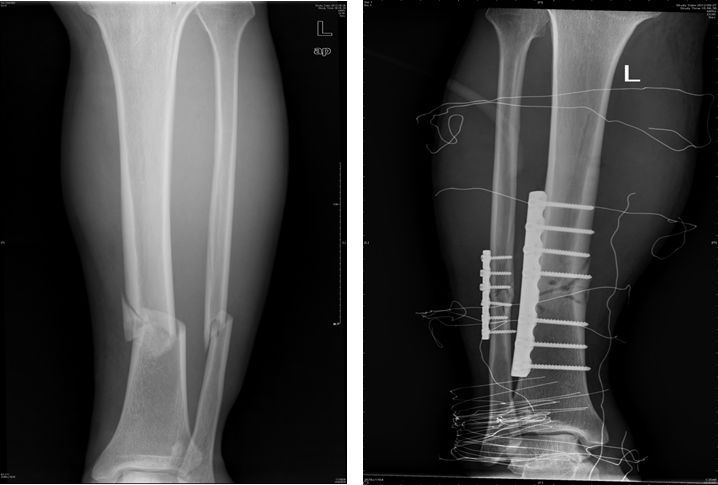

3、胫腓骨骨折

功能锻炼方法:

外固定后早期,疼痛减轻即刻进行股四头肌静止收缩运动,髌骨被动活动及足部跖趾关节和趾间关节活动。

外固定去除后,伤口愈合,可充分练习下肢各个关节活动,并逐步去拐行走。

增加髋、膝、踝关节活动练习,可做起立与坐下练习,健肢站立,患肢做髋屈伸、内收。